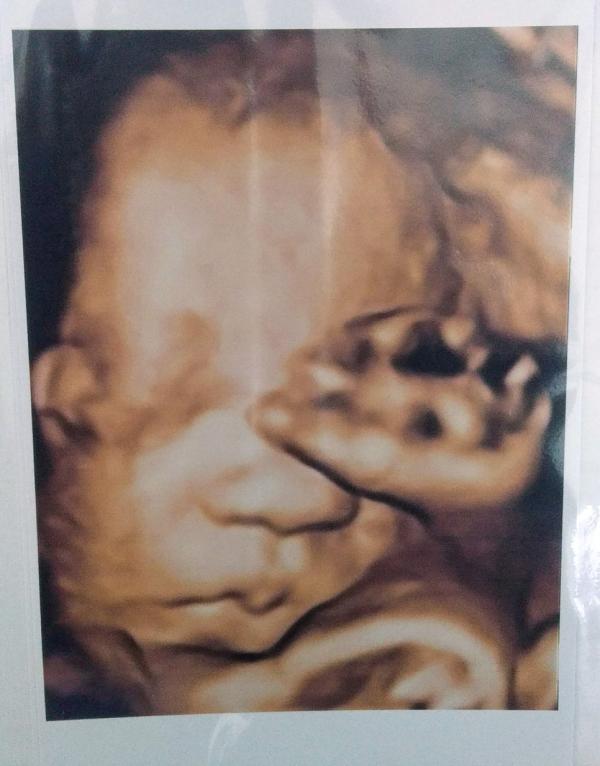

Ну что за сладкая булочка 🥰🥰 губки бантиком, точно мои❤️ мы уже 1,200г. Не отстаем, все хорошо. Со вчерашнего дня прям психует в животике, видимо с пуповиной отношения выясняет 🤪. До этого сидел так тихонечко себе, что я стала переживать, тк за январь -1,5 кг веса и +0см в окружности живота. Но оказалось зря, сынок не голодает🤞

А так да, переживём. Когда вижу пупсика на УЗИ, обо всем забываю. Да и все таки 7 месяцев у меня была идеальная Беременность, без трудностей. Осталось чуток 🤞